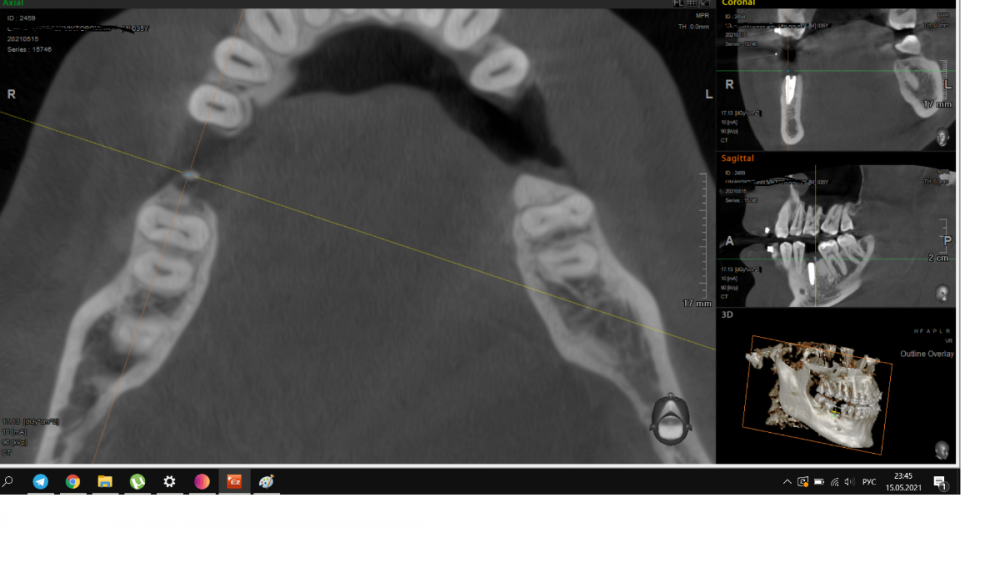

It'sGeorgy Опубликовано 15 мая, 2021 Автор Поделиться Опубликовано 15 мая, 2021 Пациент пропал на год, позвонил в клинику сегодня, отправили на кт. Сказал, на десне какой-то прыщик на десне(скорее всего, причина в этой оставленной штуки в десне) и что-то где-то там болит(сверху пульпит прям над винтом). В прошлых сообщениях забыл указать: графта не было. А вот имплантат откровенно неудачно поставил, надеюсь, десна вывезет. Да и сам имплантат, если бы сейчас ставил, выбрал Штрауманн ТЛ. 1 Ссылка на комментарий

It'sGeorgy Опубликовано 15 мая, 2021 Автор Поделиться Опубликовано 15 мая, 2021 Только что, Irouil сказал: А что,собственно, не нравится? ну язычнее надо бы...вестибулярная стенка у шейки совсем тонкая. Ну и десны после транспа с бугра много вышло, 5.5 мм по КТ(знаю, что это не всегда соответствует реальности, но все же). В таких случаях стараюсь полированной шейкой поддесневую часть выполнять, ибо любая недополировка абатмента или поддесневой части коронки будет критична. Ссылка на комментарий

Irouil Опубликовано 16 мая, 2021 Поделиться Опубликовано 16 мая, 2021 У вас по КТ и над зубами десны по пару мм. да и ничего плохого в 5 мм не было бы. Во первых, всегда можно использовать абатменты с высокой шейкой, а во вторых очень редко когда нельзя все это расформировать в широкий контур прорезывания временной коронкой. С костью все нормально, имхо 1 Ссылка на комментарий

It'sGeorgy Опубликовано 16 мая, 2021 Автор Поделиться Опубликовано 16 мая, 2021 6 часов назад, Irouil сказал: У вас по КТ и над зубами десны по пару мм. Таки да, не заметил посмотрим на этапе фдм что там с десной в итоге. 6 часов назад, Irouil сказал: а во вторых очень редко когда нельзя все это расформировать в широкий контур прорезывания временной коронкой. Обсудим этот момент с ортопедом, спасибо. Ссылка на комментарий